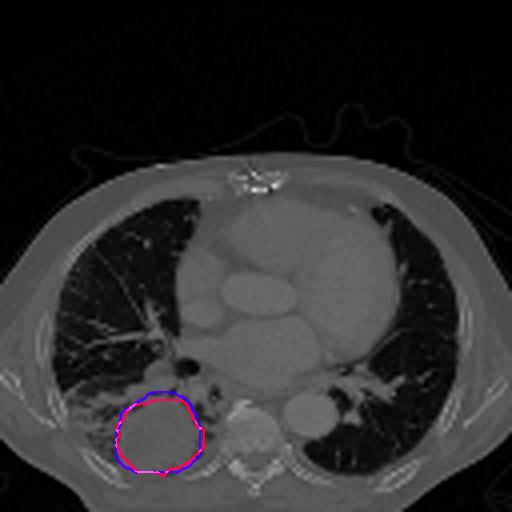

A qualitative analysis of our results reveals the strengths and weaknesses of our proposed model. In most cases, regardless of the size of the ground truth, our model predicts the tumor shapes very well. This is evident from Figure 4 where the ground truth and the prediction (by Deeply Supervised MultiResUNet) are shown in red and blue respectively. Although the tumors are in various arbitrary locations within the lung and appear in diverse sizes, the red and blue margins appear to coincide almost perfectly.

Figure 5 shows a comparison between predictions by the MultiResUNet model and Deeply supervised MultiResUNet model. It can be seen that the latter can delineate the tumor edges more accurately than the former. The ground truth (shown in red) and the prediction (shown in blue) have a more consistent alignment with each other in Deeply Supervised MultiResUNet’s prediction.